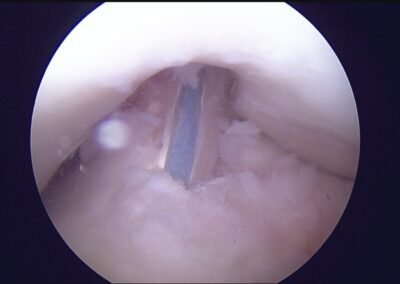

GalleryShoulder rotator cuff repair Meniscus root repair Meniscus repair Bankart repair for recurrent shoulder dislocation ACL reconstruction Machines Instruments